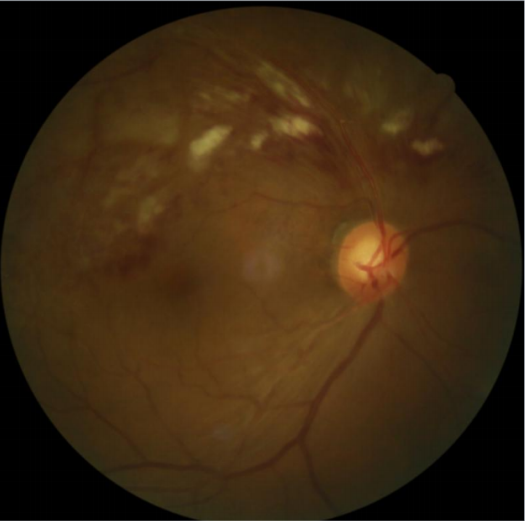

患者劉某,58歲,因右眼視力下降伴(bàn)變形1月入院。既往有高血壓病,血糖偏高病史,左眼視物(wù)不(bú)見10餘(yú)年,經過眼科主治醫(yī)師方(fāng)霏的(de)詳細檢查及(jí)眼底造(zào)影(yǐng)檢(jiǎn)查,發現是患(huàn)上了右眼視網膜分支靜脈阻塞,右眼黃斑水腫,左眼萎縮性黃斑病變(biàn)。劉大叔入院時右眼視力僅0.1 ,需要使用一種新型的生物製劑(jì)(抗 VEGF)治(zhì)療,方霏主治醫師向患者及(jí)家屬交代病情、手術(shù)必要性及相關風險 ,在排(pái)除(chú)了手術禁忌症後,患者及家屬表示同(tóng)意手術治療。次日,方霏主治醫師在患者(zhě)表麵麻醉下進行右(yòu)眼(yǎn)玻璃體藥物注射術,術後患者(zhě)無明顯特殊不適。4周後複查,右眼黃斑水腫明顯減輕,視力由0.1提高至0.6。玻璃體腔注藥術明顯改善了患者視力,患者劉大叔表示十分滿意。

術後4周眼(yǎn)底照相

術後OCT檢查提示(shì)右(yòu)眼黃斑神經上皮層厚度較前(qián)明顯變薄